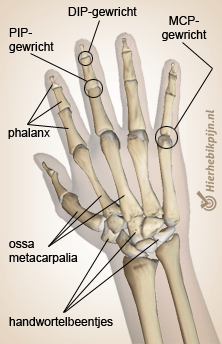

The metacarpus consists of five metacarpal bones, also known as 'ossa metacarpalia'. The ossa metacarpalia form the connection between the carpal bones of the wrist and the bones of the fingers. The fingers (also known as phalanges) consist of finger segments. The front, middle and back finger segments are called the phalanx proximalis, phalanx medialis, and phalanx distalis respectively.

The thumb has no middle phalanx (phalanx medialis). The joints between the phalanges are called the PIP, DIP, and MCP joints. Because these are hinge joints, they can normally only straighten and bend. The thumb has the characteristics of a saddle joint, which means it can move in multiple directions.